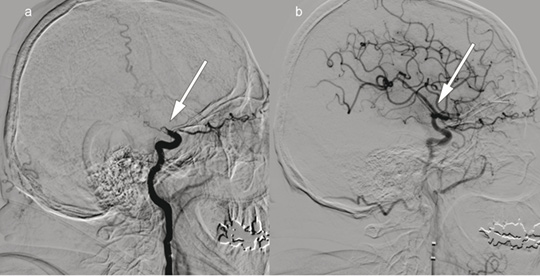

Patient 1. A man in his 70s was admitted with acute right-sided paralysis. The neurological outcome was scored on the National Institutes of Health Stroke Scale (NIHSS) to 21 points (severe cerebral infarction), and intravenous thrombolytic therapy was administered. The image to the left shows cerebral angiography with contrast injection in the left internal carotid artery, a) before and b) after embolectomy of a so-called T-occlusion (arrows) in the left carotid siphon and middle cerebral artery. The thrombus was removed and blood flow to the left hemisphere was restored 195 minutes after symptom onset. Further workup revealed atrial fibrillation and an embolic cerebral infarction in the middle cerebral artery territory. The patient received anticoagulation therapy with rivaroxaban. The NIHSS score was 0 points at follow-up three months later.